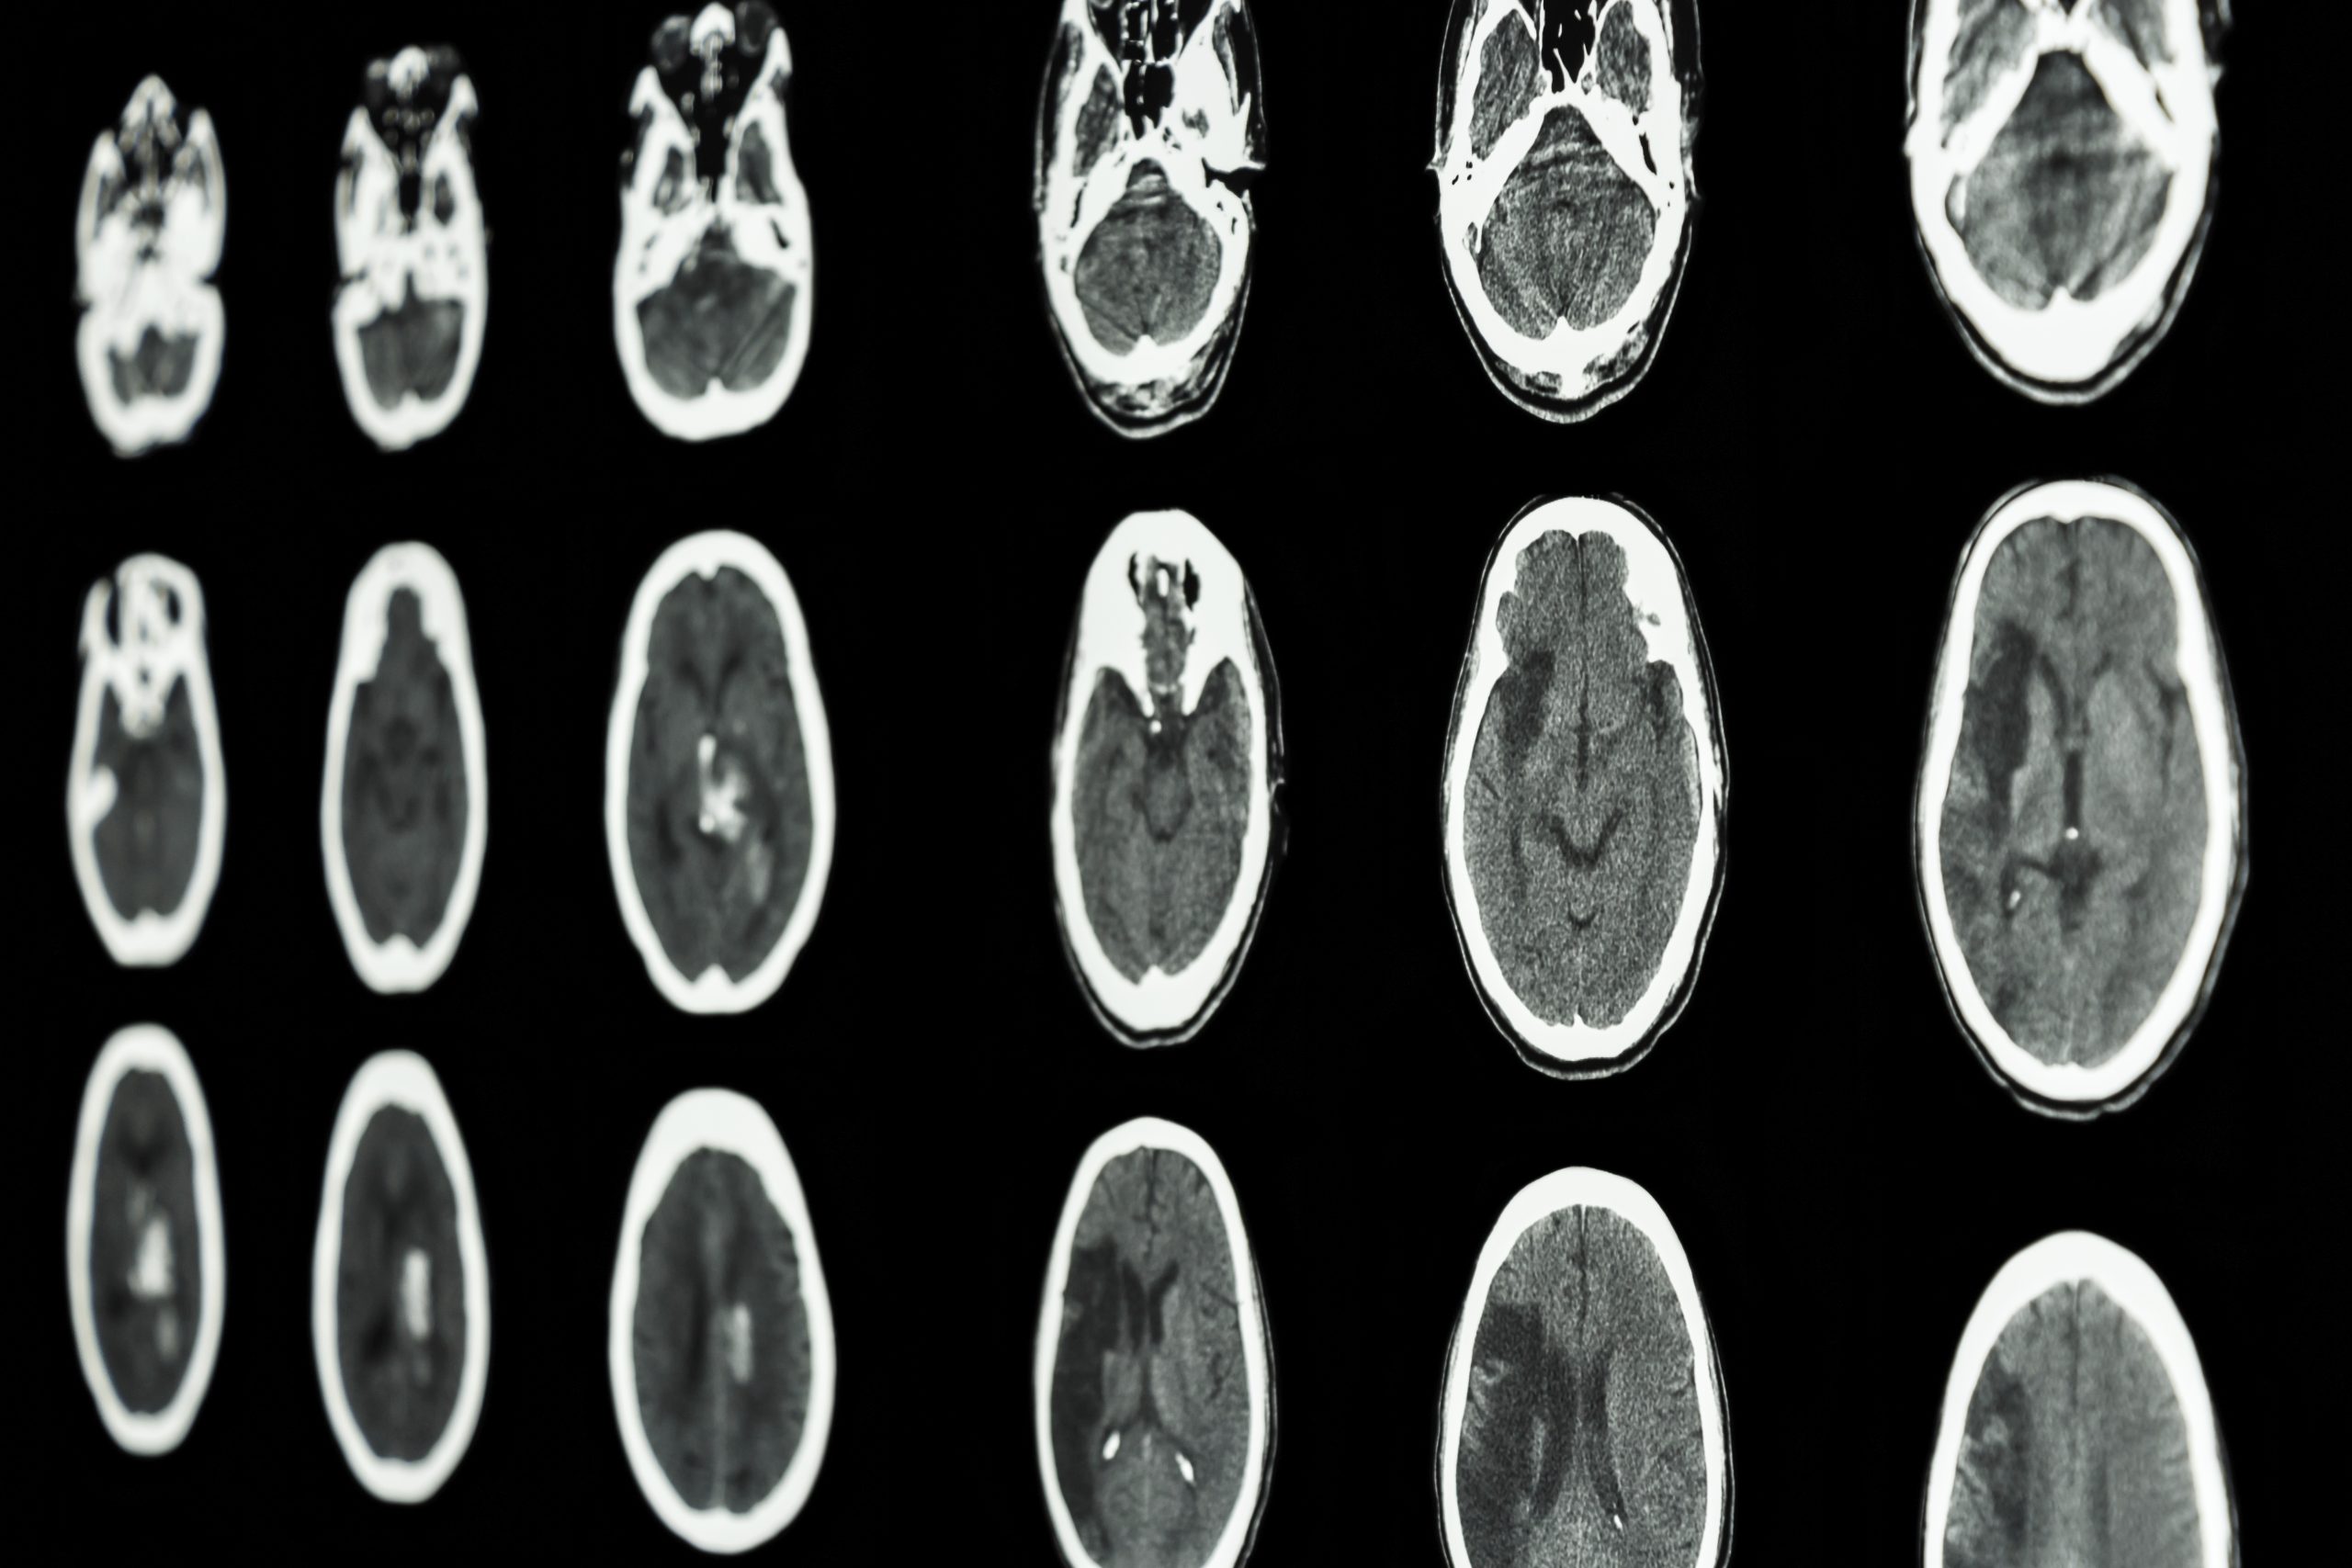

Existen dos tipos, el primero es el ACV Isquémico que se produce cuando se interrumpe el suministro de sangre hacia el cerebro. El segundo tipo es el ACV Hemorrágico que, como su nombre lo explica, consiste en el sangrado interno de este órgano.